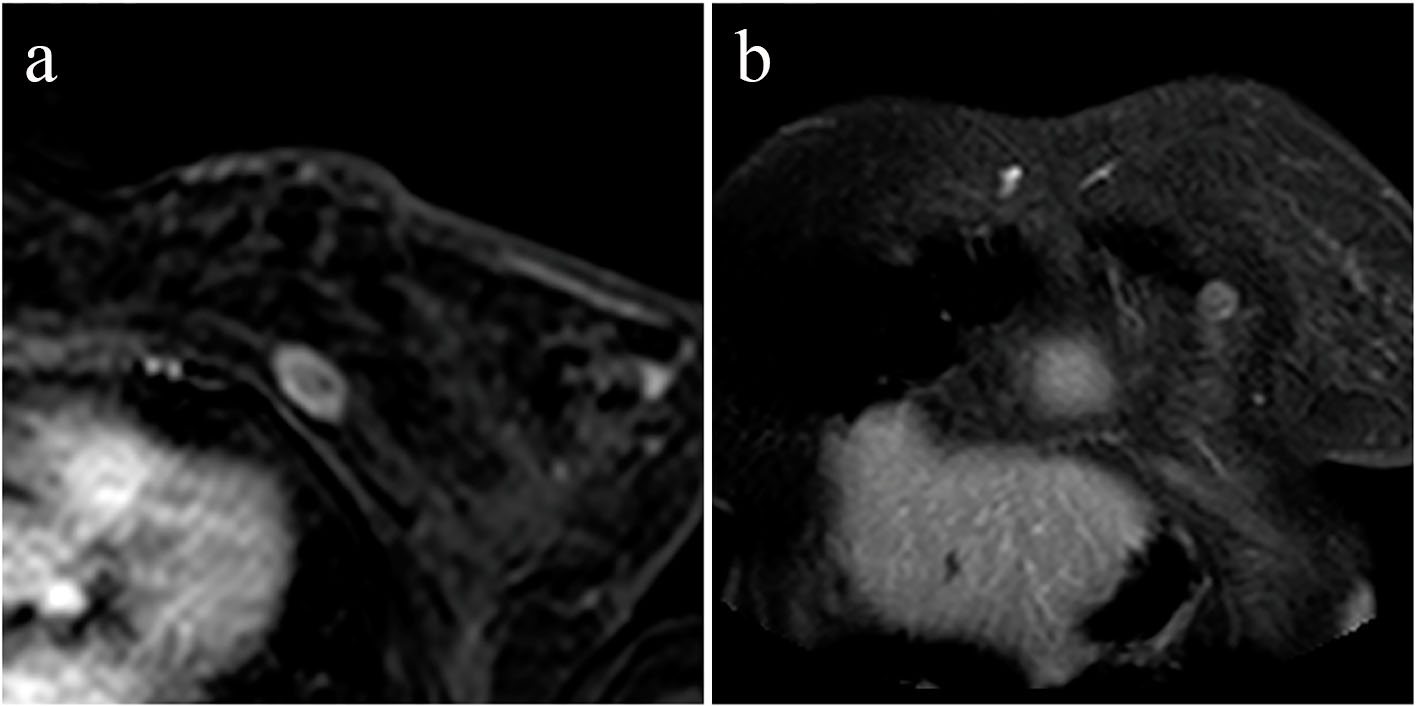

The exam showed a lesion of 27 × 13 mm at the level of the left great breastplate having heterogeneous contrastographic impregnation of intravenous contrast medium suggesting a secondary nature (Fig. 1). So we guided the patients to a surgeon to remove the lesion and a month after we were informed that the patient undergone a new surgery.

![]() Click for large image | Figure 1. Magnetic resonance imaging of the thoracic wall: post-contrast T1-weighted axial (a) and coronal (b) images showing a nodular enhancing lesion of the left major pectoralis muscle. |